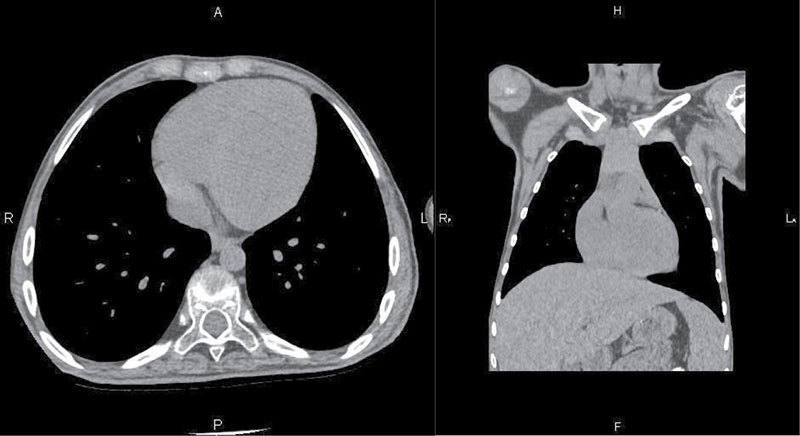

Рис. 5. Компьютерная томография органов грудной полости выполнена по стандартной детской программе на аппарате GE Revolution EVO с толщиной среза 2,5 мм и с реконструкцией по 0,625 мм. Отмечается увеличение ЛЖ

Компьютерная томография органов грудной полости: острых очаговых и инфильтративных изменений в органах грудной полости не выявлено. Размеры лимфоузлов средостения и корней легких в пределах нормальных величин. Отмечается увеличение ЛЖ (рис. 5).